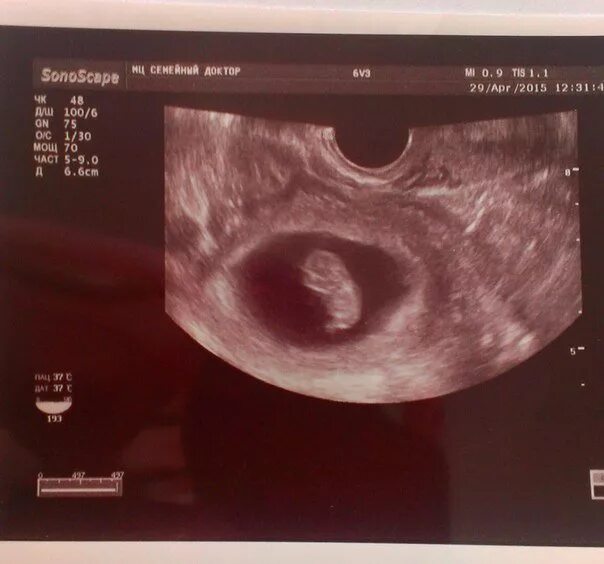

3 нед 4 дня